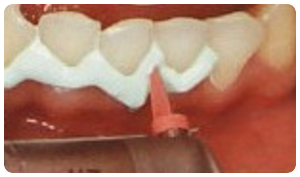

症例①

【初診時】

:年齢:30代前半

:状態:軽度歯周炎、喫煙あり、基礎疾患無し

:治療:ブラッシング指導、禁煙指導、スケーリング、ルートプレーニング、安定してからは2ヶ月ごとのメンテナンス(喫煙なし)